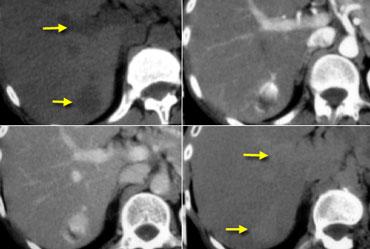

Trước tiên hãy quan sát các hình ảnh bên trái và nhận xét các kiểu ngấm thuốc.

Sau đó tiếp tục.

NECT, arterial and portal venous phase in a patient with Hepatitis C with two lesions in the liver (arrows).

Trong thì động mạch, chúng ta thấy hai tổn thương tăng sinh mạch.

Bây giờ đừng chỉ tập trung vào những hình ảnh mà bạn thấy tổn thương rõ nhất.

Bạn phải xem tất cả các hình ảnh còn lại, vì chúng cung cấp manh mối để chẩn đoán.

Các hình ảnh phía trên cho thấy một tổn thương đồng tỷ trọng với gan trên CCLVT không tiêm thuốc.

Trong thì động mạch có sự ngấm thuốc, nhưng không đậm bằng tỷ trọng máu trong lòng mạch.

Trong thì tĩnh mạch cửa, tổn thương lại đồng tỷ trọng với nhu mô gan xung quanh và không thể nhìn thấy.

Nếu chỉ có thì tĩnh mạch cửa, chắc chắn bạn sẽ bỏ sót tổn thương này.

Các hình ảnh phía dưới cho thấy một tổn thương có thể nhìn thấy trên tất cả các hình ảnh.

Bạn thấy nó trên CCLVT không tiêm thuốc và có thể nhận xét rằng nó giảm tỷ trọng so với gan.

Tuy nhiên, nếu nhìn vào tỷ trọng máu trong lòng mạch, bạn sẽ nhận thấy rằng ở tất cả các thì, tổn thương có tỷ trọng tương đương với máu trong lòng mạch.

Vậy chúng ta có một ung thư biểu mô tế bào gan ở thùy phải trên các hình ảnh phía trên và một u máu ở thùy trái trên các hình ảnh phía dưới.

Điều quan trọng là phải xem xét tất cả các thì chụp.